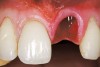

A 54-year-old non-smoking woman presented for correction of deep-wide gingival recession in the maxillary anterior (Figure 1 through Figure 3). The patient’s desires were to correct the gingival recession, balance the heights of contour of the tissues, and possibly undergo esthetic enhancement of the maxillary anterior with veneer restorations.

Figure 1  Case One Pretreatment clinical view, Case 1, maxillary right.

Figure 1